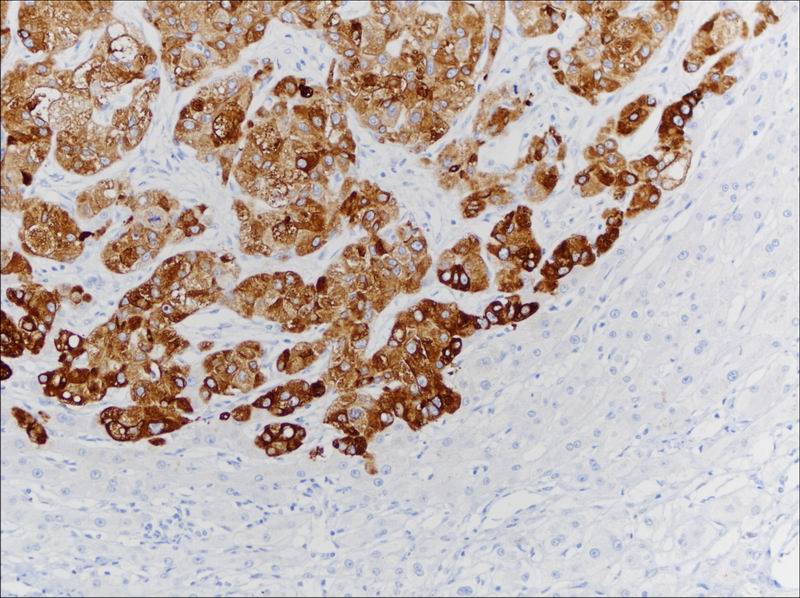

原发性肝细胞癌Glypican-3 染色,胞质阳性

GPC-3染色

王红阳院士是生物信号领域研究的杰出女将,作为我国最年轻的女院士之一,早在97年就创立了国内首个国际合作生物信号转导研究中心,肩负早日解决肝癌难题的使命,在国际上率先发现新的肝癌诊断标志物,努力克服研究初期制备单克隆抗体技术的不成熟,以其特有的执着,取得了突破性的进展,硕果累累。GPC3正是其中之一。经研究表明,GPC3在原发性肝癌的发生发展中有重要作用,可成为原发性肝癌特别是甲胎蛋白阴性肝癌的一个新标记物。经典的肝癌标记物AFP敏感性较低,在肝癌组织中表达率低,阳性表达率约为30%左右,而GPC3在肝癌中的阳性表达率可达80%。GPC3具有较高的敏感度和特异性,在肝细胞癌中高表达,在肝脏良性病变及癌前病变中不表达或低表达,有助于将微小肝癌和高级别不典型增生鉴别开来,肝穿刺活检标本行GPC3免疫组化染色可作为有效的肝癌早期鉴别诊断辅助工作,有助于预测HCC患者治疗和预后改善。